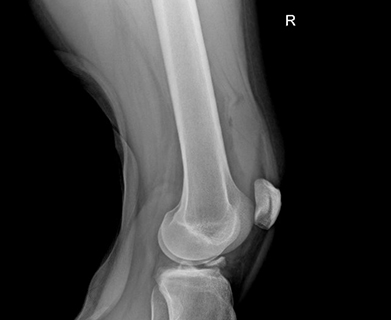

The tibial spine serves as the attachment point for the anterior cruciate ligament (ACL). It is the also the most prominent aspect within the tibial epiphyseal footprint. The tibial spine may not be fully ossified in children and young adolescents which puts them at risk for avulsion fractures of the tibial spine rather than an ACL rupture because of the partial ossification. Figure 1 shows an xray of a tibial spine avulsion fracture in a younger adult, while Figure 2 shows an xray post reduction and surgical fixation.

Figure 1